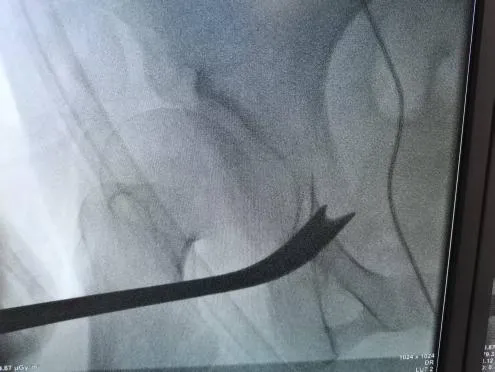

圖5-6:術中截骨